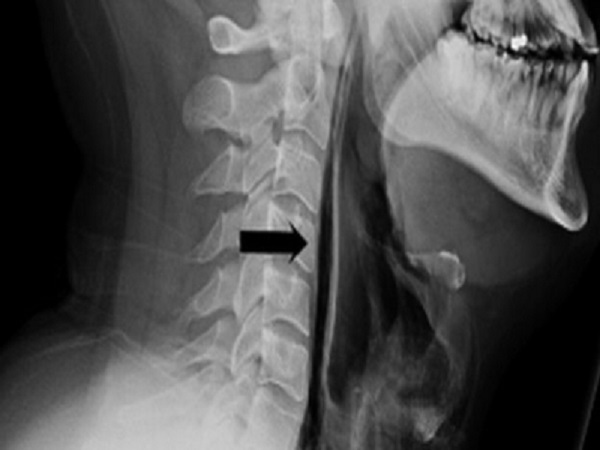

ಕೆಲ ವ್ಯಕ್ತಿಗಳಲ್ಲಿ, ವಿಶೇಷವಾಗಿ ವೃದ್ದರಲ್ಲಿ ಹೀಗೆ ಸೀನುವಿಕೆಯನ್ನು ತಡೆಯುವ ಪ್ರಯತ್ನದಿಂದ ಎದೆಗೂಡಿನ ಮೂಳೆಗಳು ಮುರಿದಿರುವ ಪ್ರಕರಣಗಳು ಕಂಡುಬಂದಿವೆ.